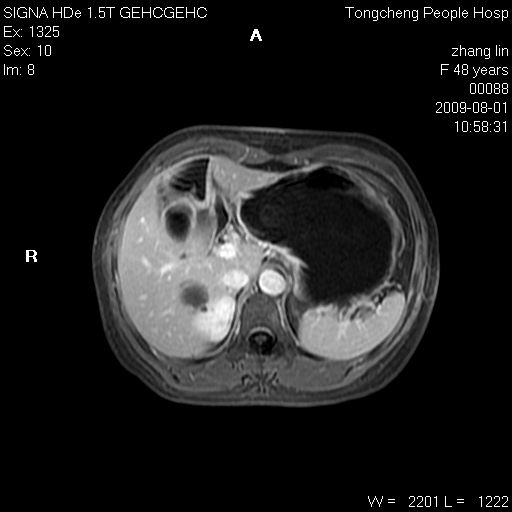

女,48岁。健康体检,彩超发现右肾占位性病变。平素健康。

临床诊断:右肾占位性病变,性质待定(囊肿?肿瘤?)。

上中腹部mr平扫+增强扫描,图像如下:

右肾上极见一类圆形病灶,t1wi呈等信号t2wi呈等高混杂信号,三期增强无强化,边界清---考虑囊肿出血。

同反相位均表现为等信号,病变无强化,考虑含蛋白的囊肿可能,弥散加权相或许有些帮助,